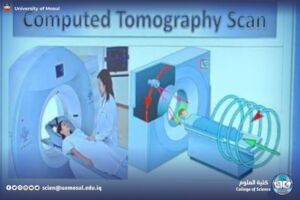

CT: شرح لكيفية أخذ مقاطع متعددة، وفكرة الـHU، ودوره في تصوير الدماغ والبطن والرئة.